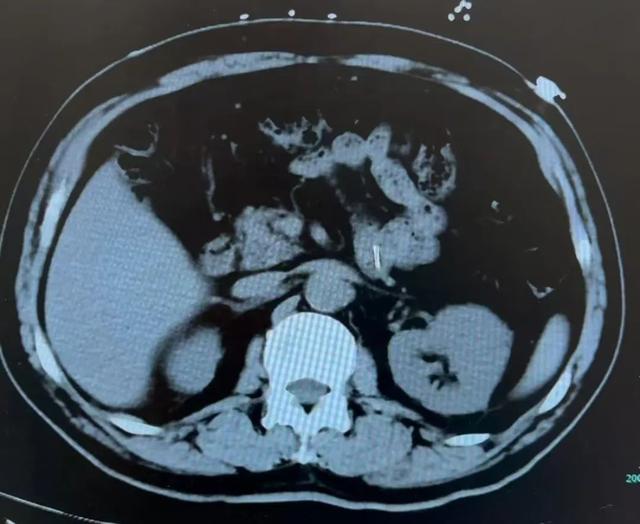

通过胸部、全腹部 CT 等检查

医生发现

异物顺着沈大爷的喉咙一路“溜达”

经过食管、胃

最终卡在了小肠的空肠部位

钻头的针尖紧贴肠壁

如果不及时处理

很有可能造成

肠穿孔或消化道大出血